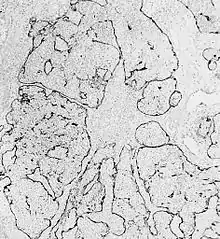

Esthesioneuroblastoma is of neurocrest origin, arising from olfactory sensory cells in the olfactory epithelium.[1] The olfactory epithelium consists of olfactory sensory cells, sustentacular cells and basal cells.[1] Esthesioneuroblastoma consists of lobular sheets with neurofibrullar fibers and rosettes.[4] Hyam's classifications are an important way of determining prognosis.[10]